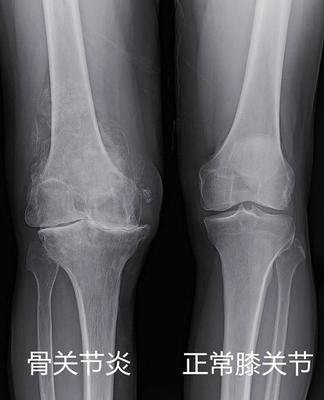

一张膝关节X光片,是膝关节炎的标准检查,也是最简单,最便宜,最有价值的。

关节间隙很狭窄了 这种一般需要换关节了

如果x光片报告上告诉你,“退行性改变”、“骨赘形成”、“间隙变窄”、“髁间嵴变尖”、“软骨下骨硬化/囊变”,这些都是关节炎患者,常常出现的。

⑤由于关节内侧和外侧的软骨受力不均,一般内侧先磨损,这样的话X线片上内侧的关节间隙就变狭窄了。越是内侧狭窄,就越是受力不均,那么很快就开始膝盖变形、慢慢变成O型腿。也有X型的,骨关节炎少见,类风湿多见。